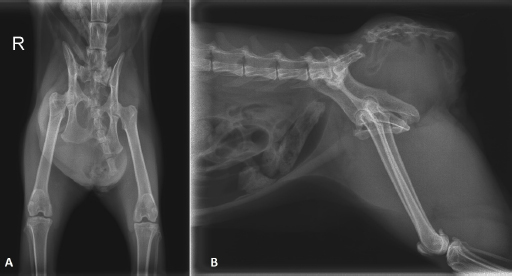

On clinical examination, the cat was in moderate general condition. On inspection, an asymmetry in the pelvic region was noted, and a fluctuant mass in the right dorso-lateral region of the pelvis could be palpated (Fig. 1). The urinary bladder could not be detected on abdominal palpation. On rectal palpation, the cat showed pain, and the mass noticeable from the outside was felt in the right dorsolateral pelvic region, and some faeces were detected. However, perineal muscle structures and anal reflexes could not be determined. The pelvis's right-lateral and ventral-dorsal radiographs revealed sacrococcygeal avulsion with a left caudodorsal dislocation of the sacral vertebrae. There was sacroiliac separation with cranial dislocation of the right hemipelvis.

Additionally, a fracture of the right ramus cranialis with dislocation and a fracture of the tabula ossis ischii with some callus formation. A round shaped, homogeneous soft tissue opacity ventral to the sacral vertebrae extends toward the right side, displacing the rectum dorsally. The urinary bladder was not visible in the caudal abdominal region (Fig. 2). There was no urinary bladder in the abdomen on ultrasound. Examination of the right sacral region with the mass revealed a fluid-filled structure directly under the skin without any evidence of sacral muscles. This structure was identified as the urinary bladder, with anechoic content and a normal wall. No urine flow could be elicited by gently massaging the urinary bladder.

Fig. 2. Ventrodorsal (A) and right-lateral (B) radiographs of the pelvis.